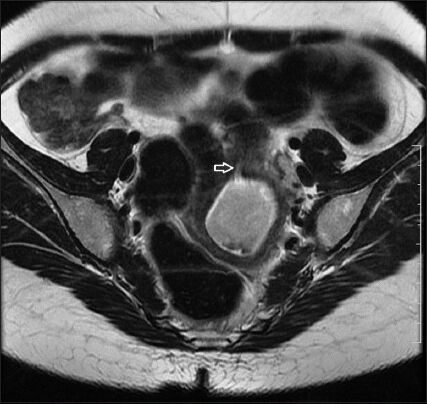

Obstructive mullerian anomalies give rise to a spectrum of clinical presentations and are uncommon in routine gynecologic practice. The patient usually becomes symptomatic in early reproductive years. Recurrent pelvic pain, dysmenorrhea, enlarging abdominopelvic mass, and abnormal vaginal discharge are the common presenting symptoms. We describe a rare case of a mullerian anomaly getting diagnosed 13 years after attaining menarche during the evaluation of postabortal sepsis. Patient presented 2 weeks following evacuation carried out for missed abortion, with acute abdominal pain, fever and foul smelling discharge per vaginum. The anomaly was identified as uterus didelphys with obstructed left hemivagina and ipsilateral renal agenesis (Herlyn-Werner-Wunderlich syndrome) complicated by pyocolpos. She was successfully managed by single-stage transvaginal septum resection under laparoscopic control.

Abstract Image